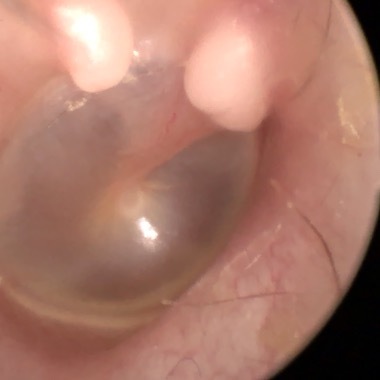

Cholesteatoma Clinical

Ear Canal

Tympanic Membrane